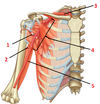

1? 2?

1: Supraspinatus muscle

2: Serratus anterior muscle

1?

1: Trapezius muscle

1?

1: Cranial nerve XI (accessory nerve)